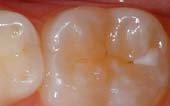

A sealant is a protective coating that is applied to the chewing surfaces (grooves) of the back teeth (premolars and molars), where four out of five cavities in children are found. This sealant acts as a barrier to food, plaque and acid, thus protecting the decay-prone areas of the teeth.

Before Sealant Applied

After Sealant Applied

Dental sealants form a solid layer of protection on top of your children’s molars to help them in the battle against tooth decay. Sealants start out as a liquid plastic that we “paint” on the chewing surface of your children’s teeth. Once dried with a curing light, sealants are barrier between the bacteria that cause cavities and your children’s deeply grooved and pitted molars.